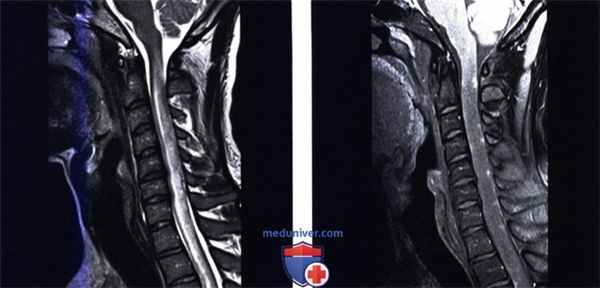

(Слева) Сагиттальный срез, Т2-ВИ: признаки диффузного отека спинного мозга в виде гиперинтенсивности Т2-сигнала с диффузным увеличением объема шейного отдела спинного мозга и облитерацией окружающего ликворного пространства.

(Справа) Сагиттальный срез, Т1-ВИ, FS с КУ: множественные узелковые очаги контрастного усиления сигнала, расположенные преимущественно в толще мягкой мозговой оболочки на протяжении продолговатого мозга и шейного отдела спинного мозга. Более выраженное поражение мягкой мозговой оболочки, характеризующееся линейными и узелковыми очагами поражения, носит название картины «плавящейся свечи».